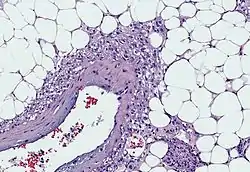

Myoid cells with clear cytoplasm spinning off of large vessels in a background of mature fat, the classic microscopic features of angiomyolipoma